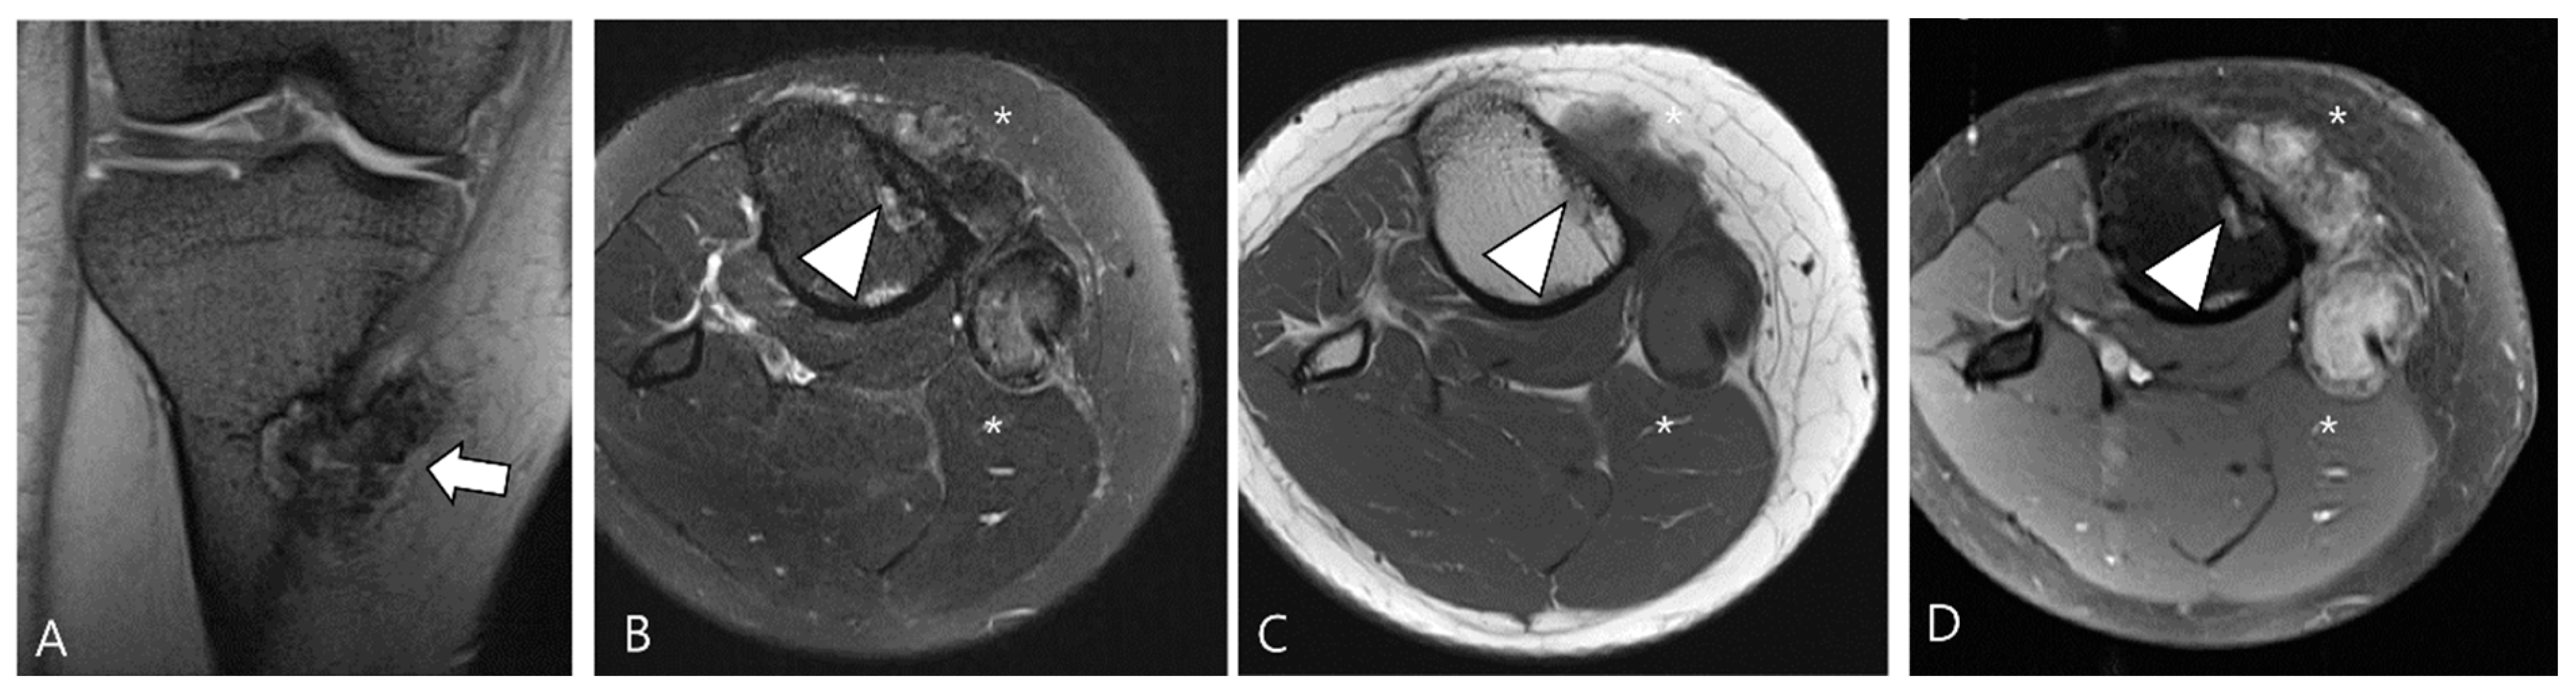

Figure 5.

Nodularity, margin, and peripheral hypointensity between two subtypes. (A) Pathology-proven L-TSGCT of the foot shows that the mass is shown as a single mass with a circumscribed margin (arrows) on axial T2WI. The mass shows the avid peripheral hypointensity (see in box) and encasement of the extensor tendon (arrowhead). (B) Pathology-proven D-TSGCT of the foot shows that the masses contain multiple distinct nodules with an infiltrative margin from the surrounding tissues (arrows) on axial T2WI. The masses show the absent peripheral hypointensity (see box) and encasement of the flexor tendon (arrowhead). Box; b = bone, yellow line = tendon.